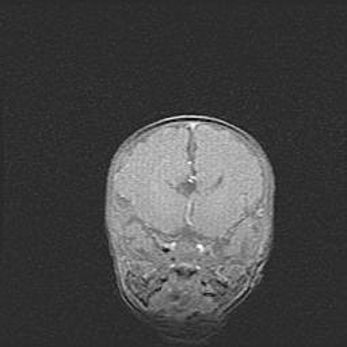

Наружная гидроцефалия с возможной атрофией височных областей.

Возраст: 28 дней

Вес: 3670 г

Пол: мужской

Окружность головы: 38 см

Срок гестации: 40 недель

Гидроцефалия головного мозга у новорожденных – это заболевание, которое характеризуется скоплением избыточного количества спинномозговой жидкости в желудочковой системе головного мозга в результате затруднения её перемещения от места выработки к месту поглощения в кровеносную систему или вследствие нарушения абсорбции. При открытой наружной форме гидроцефалии у новорожденных расширяются и переполняются субарахноидные пространства.

При нормотензивных  формах,  которые,  как  правило,  являются  следствием  перенесенных ишемических  повреждений  паренхимы  мозга,  возможно  сочетание микроцефалии  с нормотензивной гидроцефалией. В основе данных изменений лежит атрофия больших полушарий с преимущественной  локализацией  в  лобно-височных  областях.